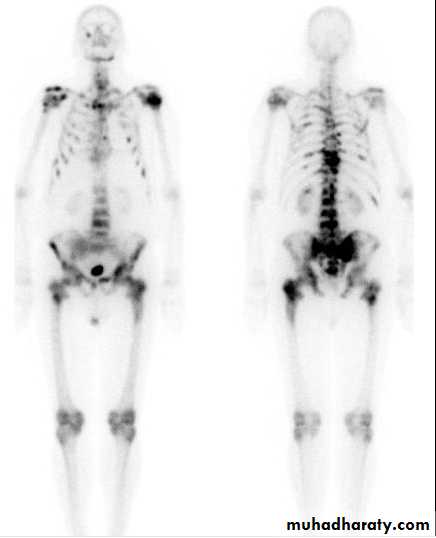

Ca Prostatebone scan